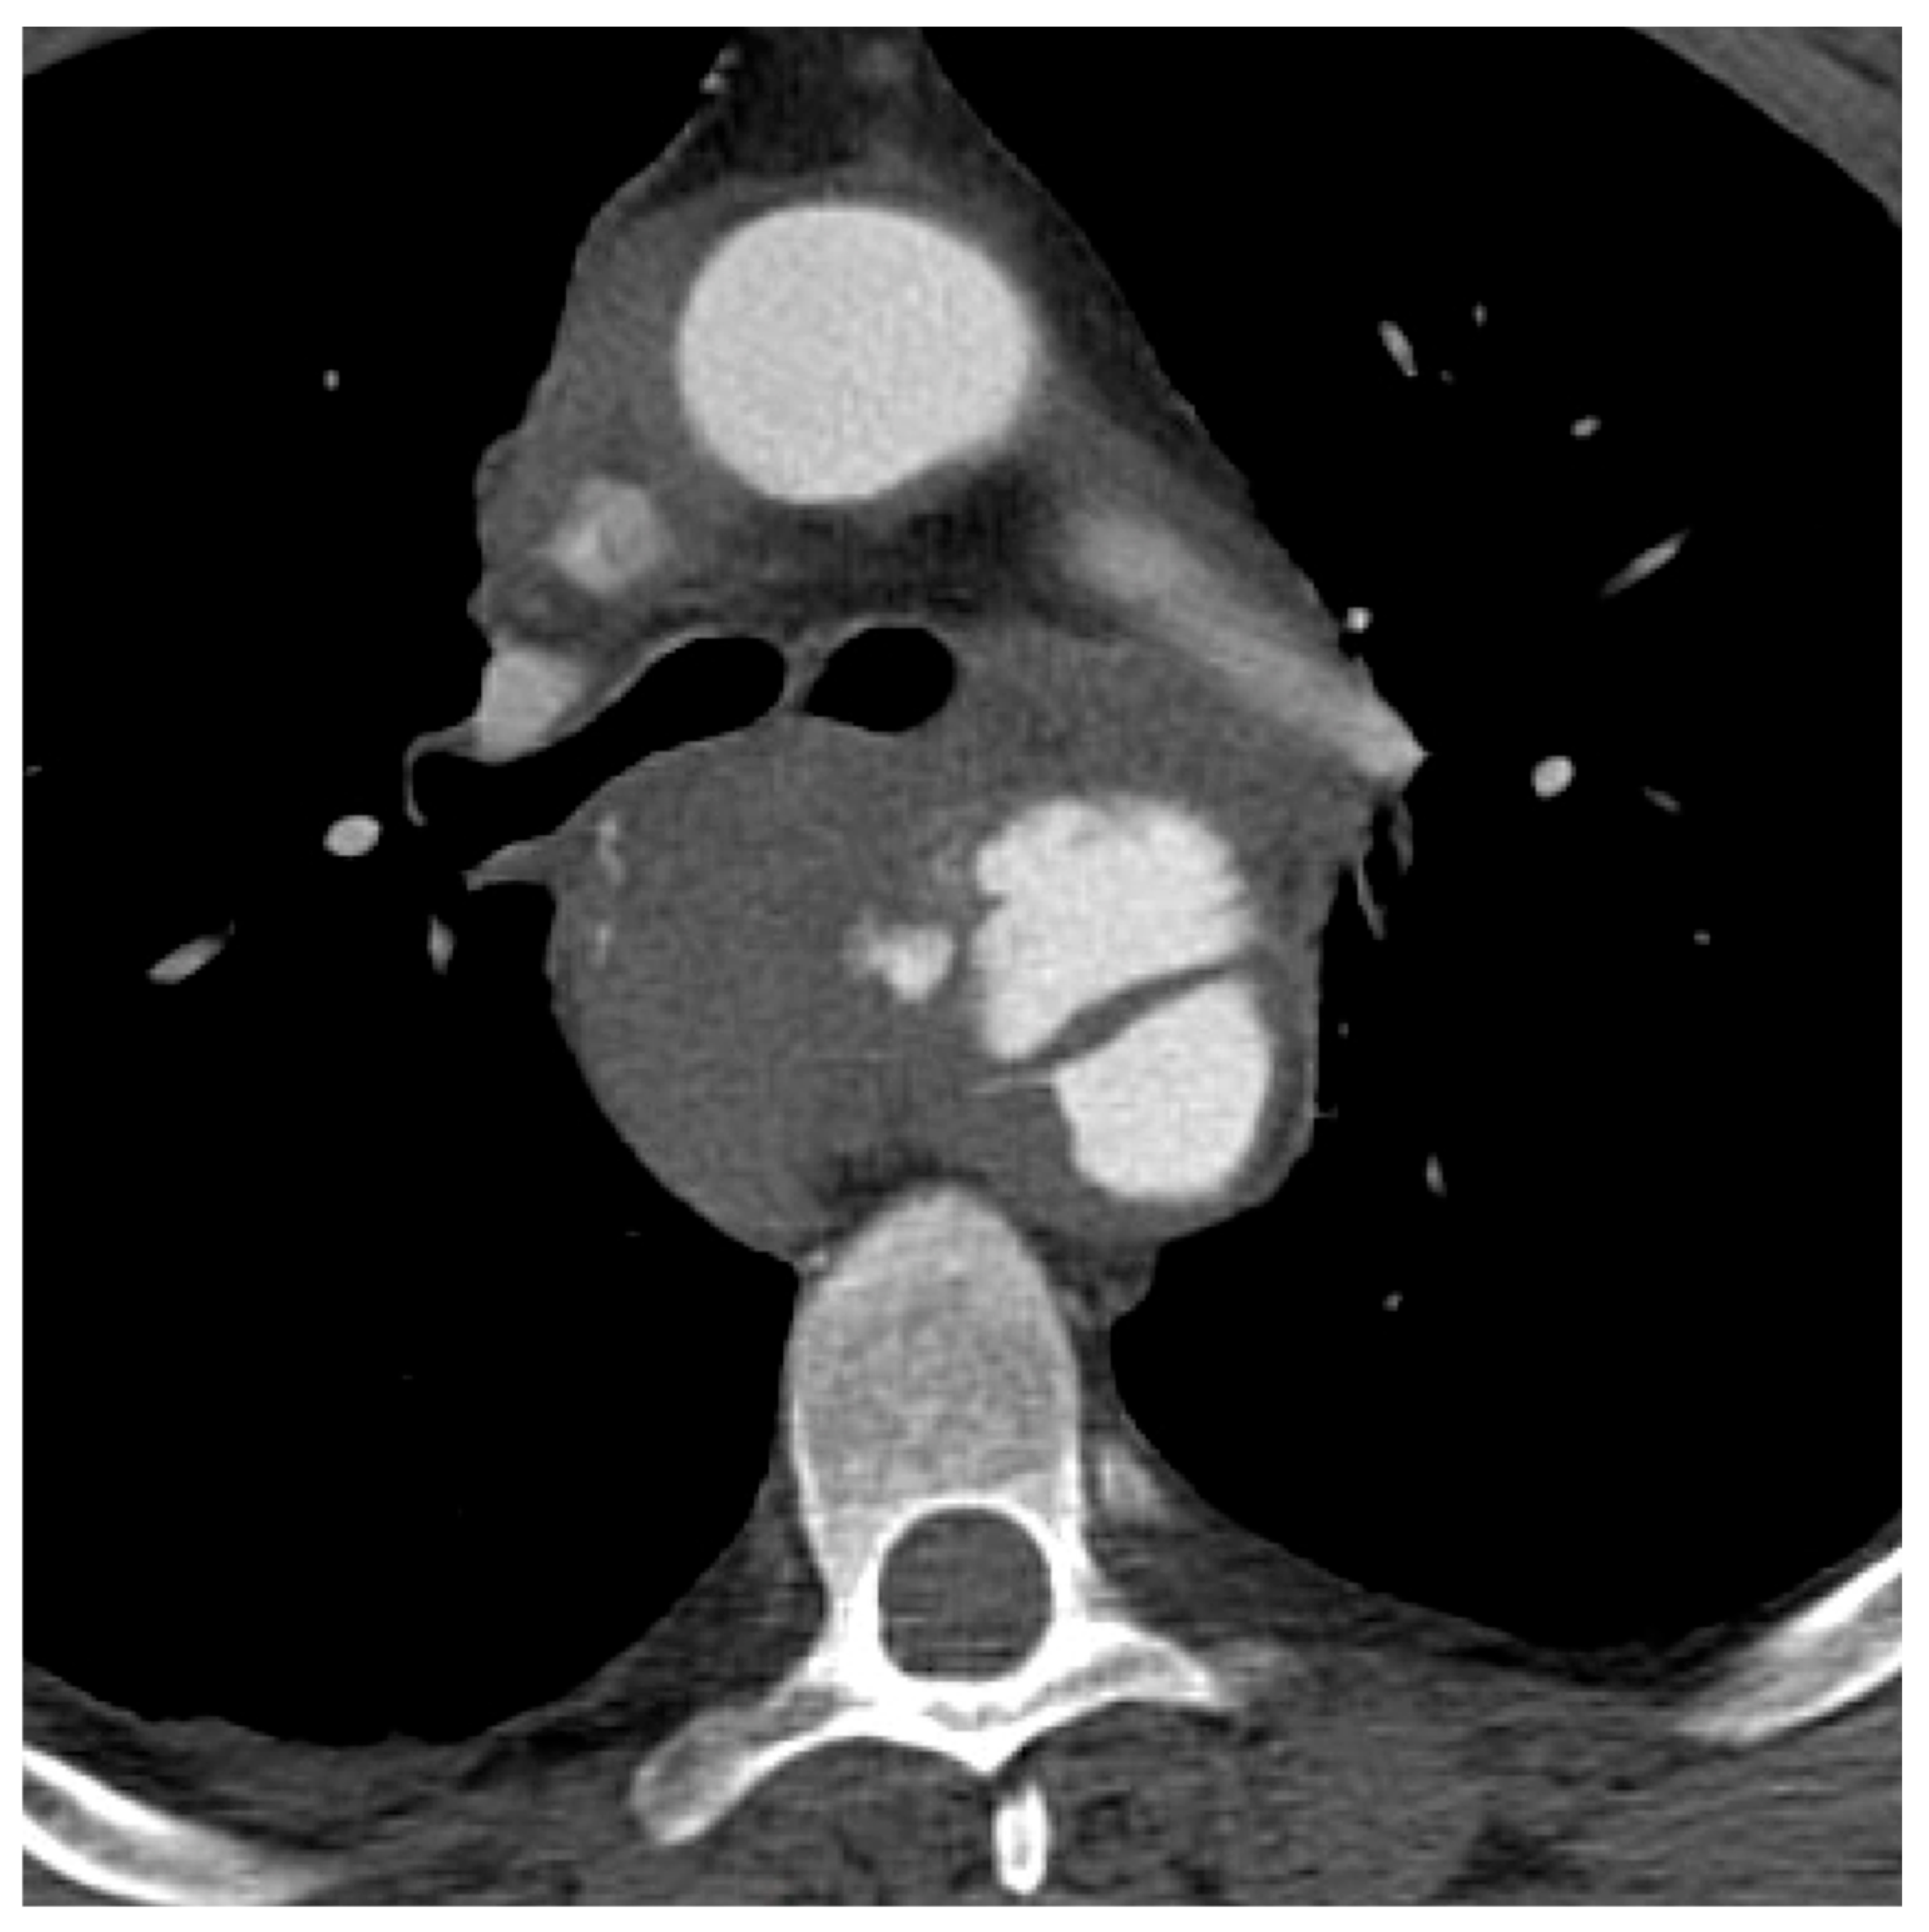

| 4 (rupture) | 2 (5%) |